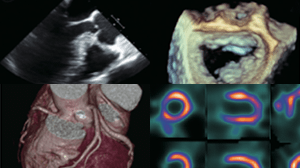

画像診断を極める

経胸壁エコー、経食道エコーおよび術中エコーを通じて外科手術やストラクチャー治療のサポートを実践します。最新機器やソフトウエアを用いた心臓CT/MRI/核医学に触れることは、画像診断の魅力を十分に感じさせてくれます。